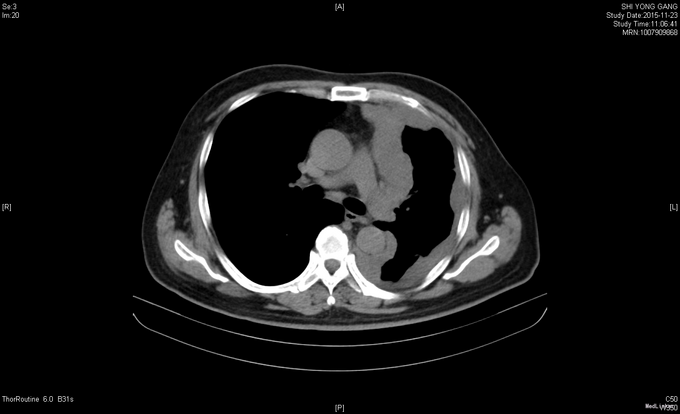

查体:左下肺呼吸音低,余查体未见明显异常。 辅查:血常规、血生化等未见明显异常;肿瘤标志物:CA125 846.80IU/ml↑、CA15-3 101.60IU/mL↑、细胞角蛋白19片段(Cyfra21-1)5.25ng/ml↑ 胸部CT示:1、左侧胸膜间皮瘤治疗后,局部心包受侵可能,心包少量积液;2、左肺高密度灶,炎症可能,淋巴管转移待排;3、左侧胸腔少量积液左肺膨胀不全;4、纵隔多发稍增大淋巴结。腹部CT示:1、腹膜后多发稍大淋巴结;2、脾脏肿大;3、右肾多发囊肿;4、左侧胸膜不规则增厚,恶性病变可能,请结合临床;心包少量积液。头颅MRI、骨骼ECT未见明显异常。

诊治经过:入院后完善相关检验检查,结合病史及外院胸膜活检病理结果,考虑患者恶性胸膜间皮瘤诊断明确,排除有关禁忌症后,于11-01起行AP方案化疗:AP:培美曲塞 1g d1+顺铂 130mg d1,化疗后无特殊不良反应,经请示上级医师同意后予办理出院。